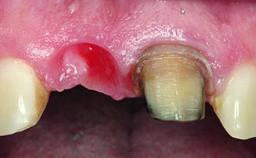

A 32-year-old female Caucasian patient with a compromised maxillary right central incisor was referred to us by a general dentist. Her chief complaints were discomfort and mobility of tooth 11 with unsatisfactory esthetics due to discoloration. The patient reported a previous trauma, some years earlier, as the origin of pathology on the afflicted tooth. Anamnesis was negative for any other dental or periodontal pathology in the remaining dentition. The patient did not take any medication and reported to be a light smoker (5–10 cigs/day). She had high esthetic expectations of her treatment. The extraoral examination revealed a high smile line with full exposure of her maxillary teeth and surrounding soft tissue in the area between the second premolars.

Lip Line No exposure of papillae Exposure of papillae Full exposure of mucosa margin

Periodontal Phenotype Low-scalloped, thick Medium-scalloped, medium-thick High-scalloped, thin

Soft Tissue Anatomy Intact Defective